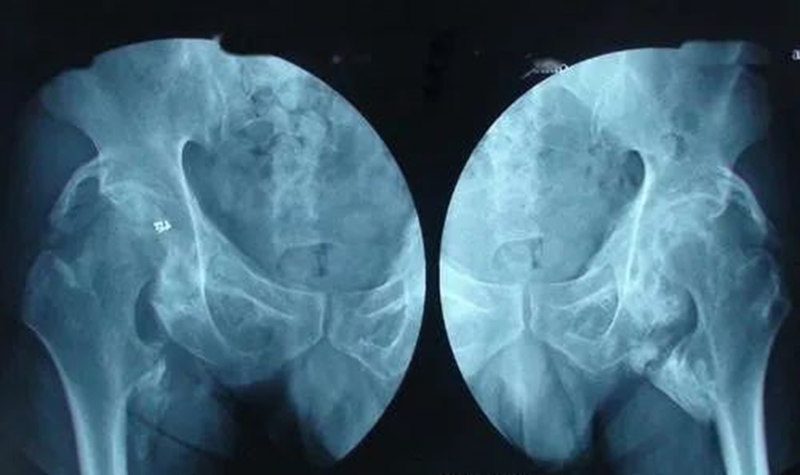

超哥,髖部盂唇撕裂軟骨輕微磨損,股四頭肌萎縮嚴(yán)重,髖關(guān)節(jié)活動度不夠該怎么康復(fù)鍛煉,可不可以走樓梯下蹲

骨化性肌炎的臨床特點

1.常有關(guān)節(jié)損傷史,多見于青少年。2.早期以關(guān)節(jié)活動時疼痛,局部溫度升高,腫脹,關(guān)節(jié)活動逐漸受限。?????3.在關(guān)節(jié)周圍可以摸到異常骨塊,該骨塊可逐漸增大,以后又可緩慢回縮至骨塊成熟?!痉派鋵W(xué)表現(xiàn)】軟組織的放射線檢查在發(fā)病最初的2周后并無異常表現(xiàn)。在2~4周的時間內(nèi)鈣化逐漸變得明顯,完全成熟的病變可以在大約14周后看到,在創(chuàng)傷后大約5個月,骨化的過程完全停止。

骨化性肌炎的發(fā)病機制

1.骨化性肌炎是由于關(guān)節(jié)內(nèi)或關(guān)節(jié)附近發(fā)生骨折、脫位后,固定不良、反復(fù)粗暴的整復(fù)骨化性肌炎手法、被動活動?;蛟诿撐缓蟛痪谩⒐悄ぶ匦屡c骨相連之前,過早地進(jìn)行被動和強力活動,使纖維組織增生,骨或骨化生所致。2.病變組織多為肌肉,也可為筋膜、肌腱、骨膜。